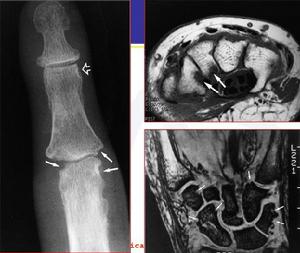

![FELTY綜合症[費爾蒂綜合徵] FELTY綜合症[費爾蒂綜合徵]](/img/7/33a/nBnauM3X2UTM1YjN4EDM5QjNyITMyYjN0YjMwADMwAzMxAzLxAzLzAzLt92YucmbvRWdo5Cd0FmLxE2LvoDc0RHa.jpg)